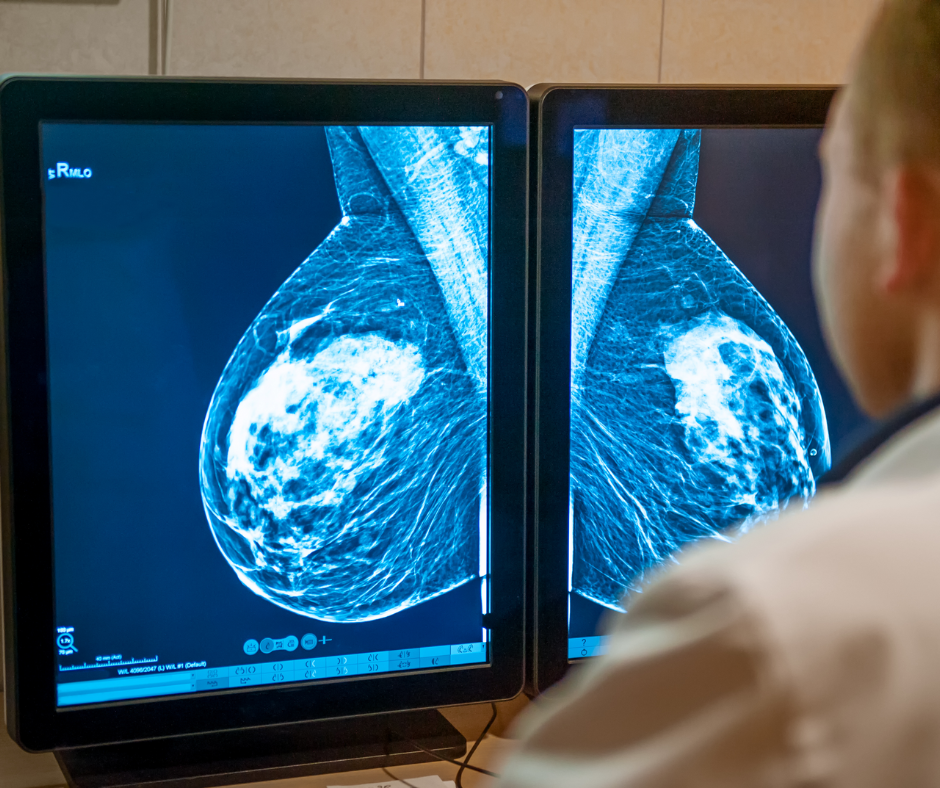

Can ChatGPT Provide Appropriate Information on Mammography and Other Breast Cancer Screening Topics?

Researchers found that ChatGPT offered appropriate responses to 22 out of 25 patient-oriented questions on mammography screening, dense breasts, BI-RADS scoring and other topics related to breast cancer screening and prevention.